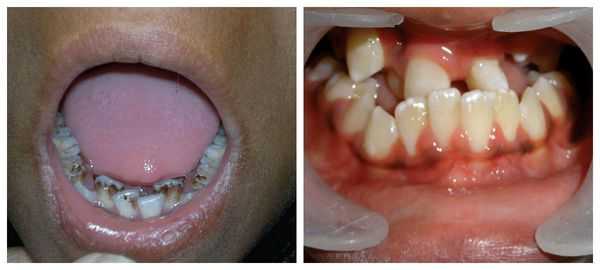

Перечисленные лицевые аномалии могут сопровождаться нарушением слуха, неправильной закладкой и прорезыванием зубов и другими нарушениями, которые могут повлиять на психофизическое развитие ребёнка.

В целом расщелины лица и/или нёба, недоразвитие верхней и нижней челюсти, лицевых мышц, скуловой и/или височной костей способны вызывать проблемы с зубами, трудности при кормлении, нарушение речи и изменение эстетических параметров лица.

Также характерно уменьшение размера глазных яблок (микрофтальмия), косоглазие, атрезия радужки, катаракта. Около 50% пациентов с болезнью Гольденхара имеют высокое готическое небо, широкий рот (макростомию), расщепление языка, аномальный прикус, отсутствие части зубов. В 40% случаев отмечаются косолапость, аномалии позвоночника (сколиоз, spina bifida), искривление ребер. У 30% больных возникают врожденные патологии внутренних органов: пороки сердца, гипоплазия легких, дисплазия почек.